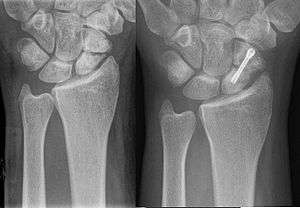

Metal plates, pins, screws, and rods, that are screwed or driven into a bone, are used to stabilize the broken bone fragments.